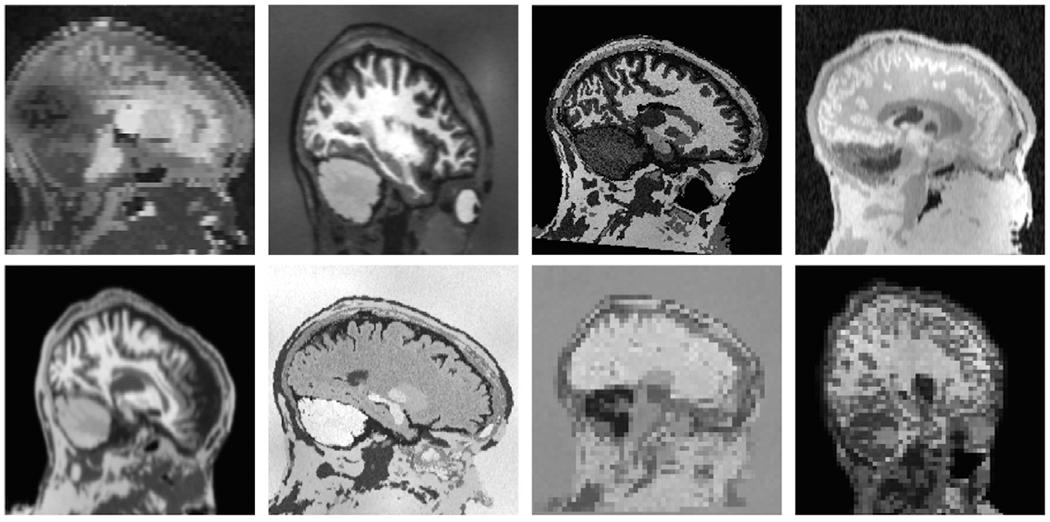

The removal of non-brain signal from magnetic resonance imaging (MRI) data, known as skull-stripping, is an integral component of many neuroimage analysis streams. Despite their abundance, popular classical skull-stripping methods are usually tailored to images with specific acquisition properties, namely near-isotropic resolution and T1-weighted (T1w) MRI contrast, which are prevalent in research settings. As a result, existing tools tend to adapt poorly to other image types, such as stacks of thick slices acquired with fast spin-echo (FSE) MRI that are common in the clinic. While learning-based approaches for brain extraction have gained traction in recent years, these methods face a similar burden, as they are only effective for image types seen during the training procedure. To achieve robust skull-stripping across a landscape of imaging protocols, we introduce SynthStrip, a rapid, learning-based brain-extraction tool. By leveraging anatomical segmentations to generate an entirely synthetic training dataset with anatomies, intensity distributions, and artifacts that far exceed the realistic range of medical images, SynthStrip learns to successfully generalize to a variety of real acquired brain images, removing the need for training data with target contrasts. We demonstrate the efficacy of SynthStrip for a diverse set of image acquisitions and resolutions across subject populations, ranging from newborn to adult. We show substantial improvements in accuracy over popular skull-stripping baselines - all with a single trained model. Our method and labeled evaluation data are available at https://w3id.org/synthstrip.